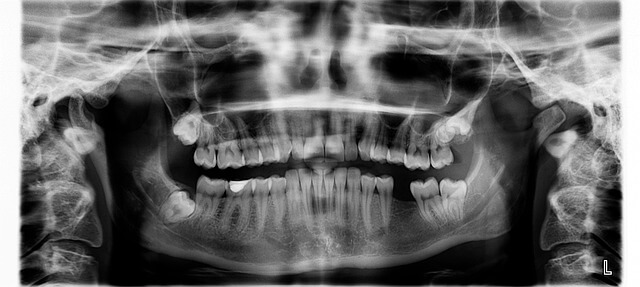

눈앞에 펼쳐진 상악동 거상술의 비밀, 초보자도 놀랄 사기급 꿀팁 대공개! 상악동 거상술은 윗턱 어금니 부위의 부족한 뼈를 인공뼈로 채워 임플란트 성공률을 획기적으로 높이는 핵심 시술입니다. 이 한 수술로 뼈가 얇아 임플란트가 어려웠던 문제를 단번에 해결할 수 있죠. 상악동 거상술은 풍부한 임상 경험과 숙련된 의료진의 손길이 필요하지만, 그만큼 확실한 결과를 약속합니다. 지금 바로 상악동 거상술 정보를 확인하고, 자신감을 갖고 건강한 미소를 만들어 보시기 바랍니다. 상악동 거상술, 더 이상 미루지 말고 집에서 편하게 알아보세요!

*상악동 거상술 비용은 생각보다 다양한 요소에 따라 크게 달라집니다. *수술의 범위, 사용되는 뼈 이식 재료, 마취 방식 등이 대표적인 변수죠. *제가 직접 조사해보니 상악동 거상술은 환자의 뼈 상태와 건강, 의료진의 노하우에 맞춰 개별 맞춤식으로 진행되기 때문에 비용 차이가 크게 나는 경우가 많습니다. *쉽게 말해, 뼈가 많이 부족한 분의 상악동 거상술은 더 넓은 부위에 뼈를 채워야 해서 비용이 더 늘어날 수 있습니다. *그래서 상악동 거상술을 검토 중이라면 개인 맞춤 진단을 통한 세부 견적을 꼭 받아보는 게 중요해요.

2. 실제 상악동 거상술 비용 범위는?